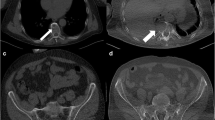

In our experience too the superiority of the CT examination was well demonstrated. Owing to its better spatial and contrast resolution, CT allowed the detection of small skull, vertebral and pelvic lesions undetectable or easily overlooked in X-ray examinations (Fig. 6A-a–d).

A Axial CT images nicely depict small lytic lesions within the skull (a), in the pelvis (b), in a thoracic vertebra and the adjacent rib (c), undetectable or easily overlooked in a X-ray examination; reformatted sagittal CT image shows numerous lytic lesions and multiple compression fractures in the thoracic and lumbar spine (d); reformatted coronal CT image shows an endomedullary soft tissue nodule in the humerus with minimal scalloping (e); axial CT image shows a huge solid mass destroying the thoracic vertebra and the rib and extending in the adjacent soft tissue of the thoracic apex (f). B Incidental finding: a 16 mm left pulmonary nodule (g) and a right lower lobe apical segment consolidation (h)

In addition, endomedullary and extraosseous nodules were easily recognized (Fig. 6A-e, f).

Moreover in our population, WBLDMDCT assessed several incidental findings, especially thoracic abnormalities. They have been mentioned in the report. Most of them did not have a clinical impact; nevertheless, in two cases a prompt diagnostic/therapeutic workup was elicited (Fig. 6B). Overall, in agreement with the above mentioned authors, we also found such an improvement in diagnostic accuracy of CT examination to justify the dose increment.